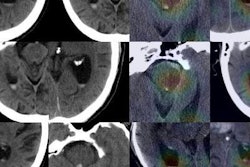

After training a convolutional neural network (CNN) to detect ICH on noncontrast head CT scans, the MGH researchers found that it produced a high level of performance. They then wanted to assess how the system would perform in the real world.

Lee and colleagues gathered 2,606 consecutive cases of noncontrast head CT performed at their emergency department from September to November 2017. The cases were labeled as positive or negative for ICH using natural language processing (NLP) of clinical reports. Of the 2,606 cases, 163 were positive for intracranial hemorrhage, according to the NLP analysis.

The researchers then delved further into data to find out why the model's performance dropped. A neuroradiologist with more than 20 years of experience reviewed 21 false-negative cases and found that eight did not contain acute bleeding (report hedging). Eleven cases contained small bleeding not visualized on axial CT images and two were small (3 mm and 10 mm) acute subdural hematomas, Lee said.